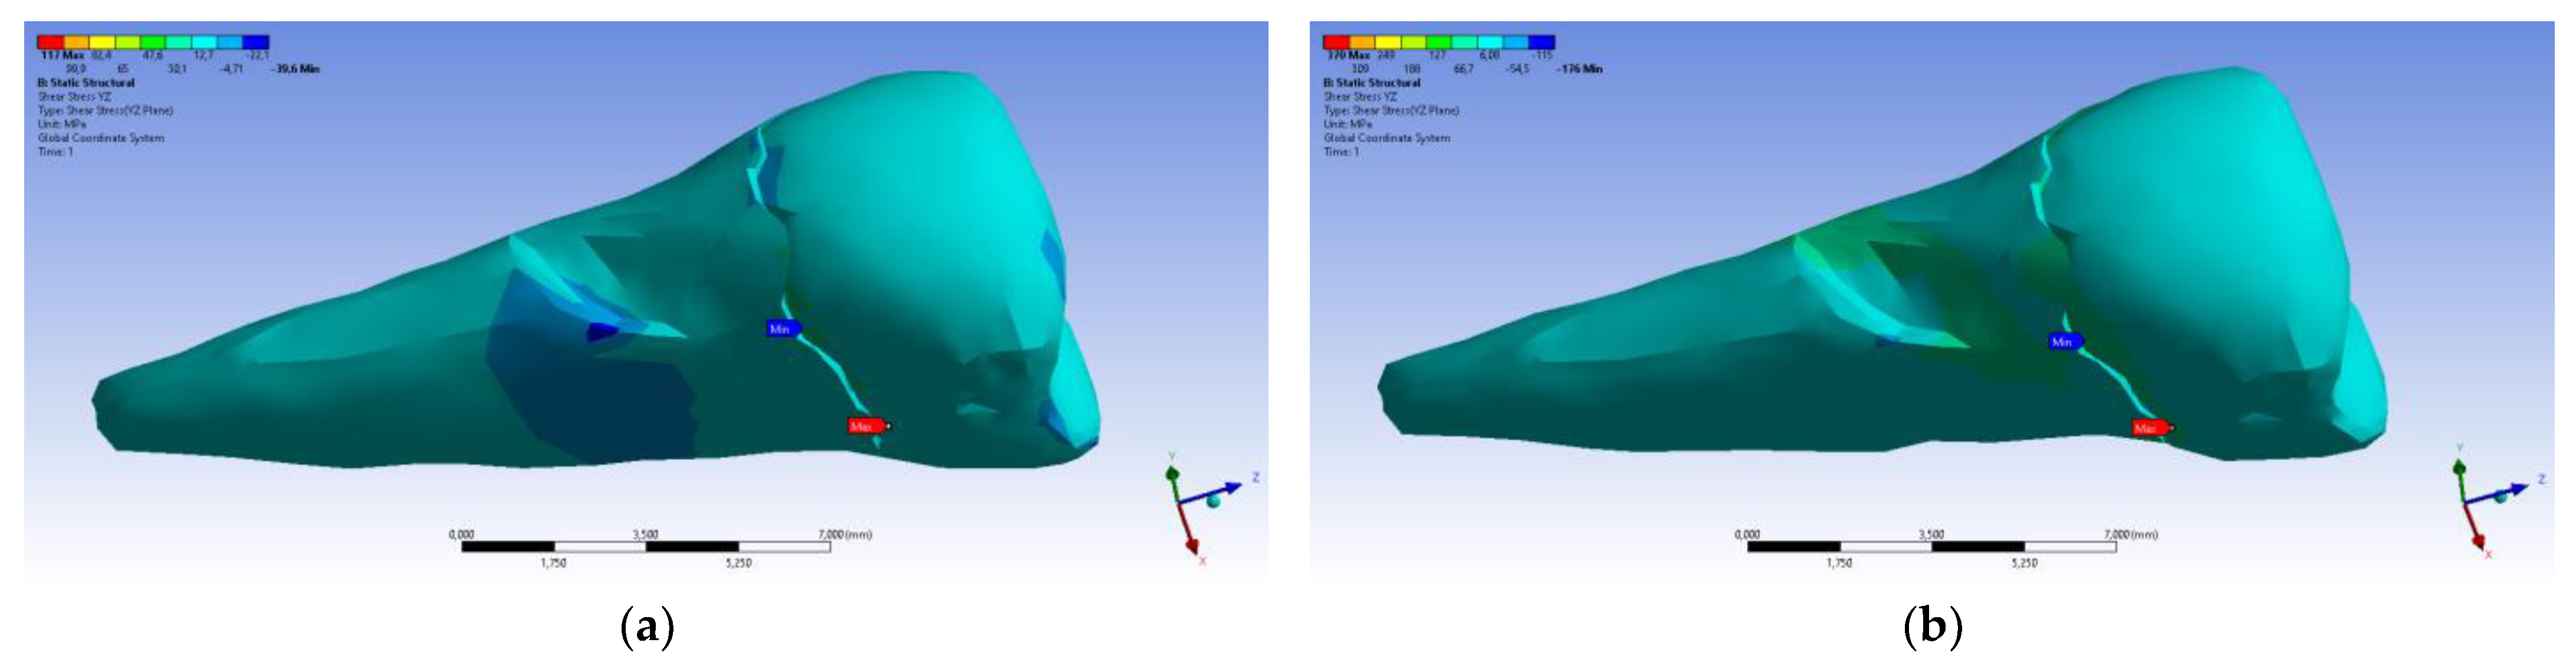

3. Finite Element Analysis (FEA) of Mandibular Right Premolars

| Total Deformation | Deformation in X Direction | Deformation in Y Direction | Deformation in Z Direction | Equivalent Stress | Normal Stress X | Normal Stress Y | Normal Stress Z | Maximum Main Stress | Minimum Main Stress | Tangential Stress XY | Tangential Stress YZ | Tangential Stress XZ | |

|---|---|---|---|---|---|---|---|---|---|---|---|---|---|

| Minimum | 0 mm | −4.24 × 10−3 mm | −2.52 × 10−2 mm | −1.56 × 10−2 mm | 1.01 × 10−6 MPa | −35.6 MPa | −57.1 MPa | −104 MPa | −15.2 MPa | −152 MPa | −43.7 MPa | −39.6 MPa | −56.3 MPa |

| Maximum | 2.77 × 10−2 mm | 3.57 × 10−3 mm | 6.98 × 10−4 mm | 4.78 × 10−3 mm | 248 MPa | 61.5 MPa | 177 MPa | 72.2 MPa | 195 MPa | 21.4 MPa | 44.2 MPa | 117 MPa | 22.2 MPa |

| Minim. in | Cementum | Cementum | Enamel | Enamel | Cementum | Cementum | Enamel | Enamel | Enamel | Cementum | Enamel | Enamel | Cementum |

| Maxim. in | Enamel | Enamel | Cementum | Enamel | Cementum | Enamel | Enamel | Enamel | Enamel | Enamel | Cementum | Cementum | Cementum |

| Total Deformation | Deformation in X Direction | Deformation in Y Direction | Deformation in Z Direction | Equivalent Stress | Normal Stress X | Normal Stress Y | Normal Stress Z | Maximum Main Stress | Minimum Main Stress | Tangential Stress XY | Tangential Stress YZ | Tangential Stress XZ | |

|---|---|---|---|---|---|---|---|---|---|---|---|---|---|

| Minimum | 0 mm | −6.1 × 10−3 mm | −9.02 × 10−2 mm | −3.99 × 10−2 mm | 1.02 × 10−6 MPa | −112 MPa | −199 MPa | −278 MPa | −65.5 MPa | −470 MPa | −148 MPa | −176 MPa | −178 MPa |

| Maximum | 9.28 × 10−2 mm | 1.83 × 10−2 mm | 1.38 × 10−3 mm | 3.12 × 10−2 mm | 780 MPa | 61.5 MPa | 649 MPa | 304 MPa | 704 MPa | 73.8 MPa | 134 MPa | 370 MPa | 78.6 MPa |

| Minim. in | Cementum | Cementum | Enamel | Enamel | Cementum | Cementum | Enamel | Enamel | Enamel | Cementum | Enamel | Enamel | Cementum |

| Maxim. in | Enamel | Enamel | Cementum | Enamel | Cementum | Enamel | Enamel | Enamel | Enamel | Enamel | Cementum | Cementum | Cementum |